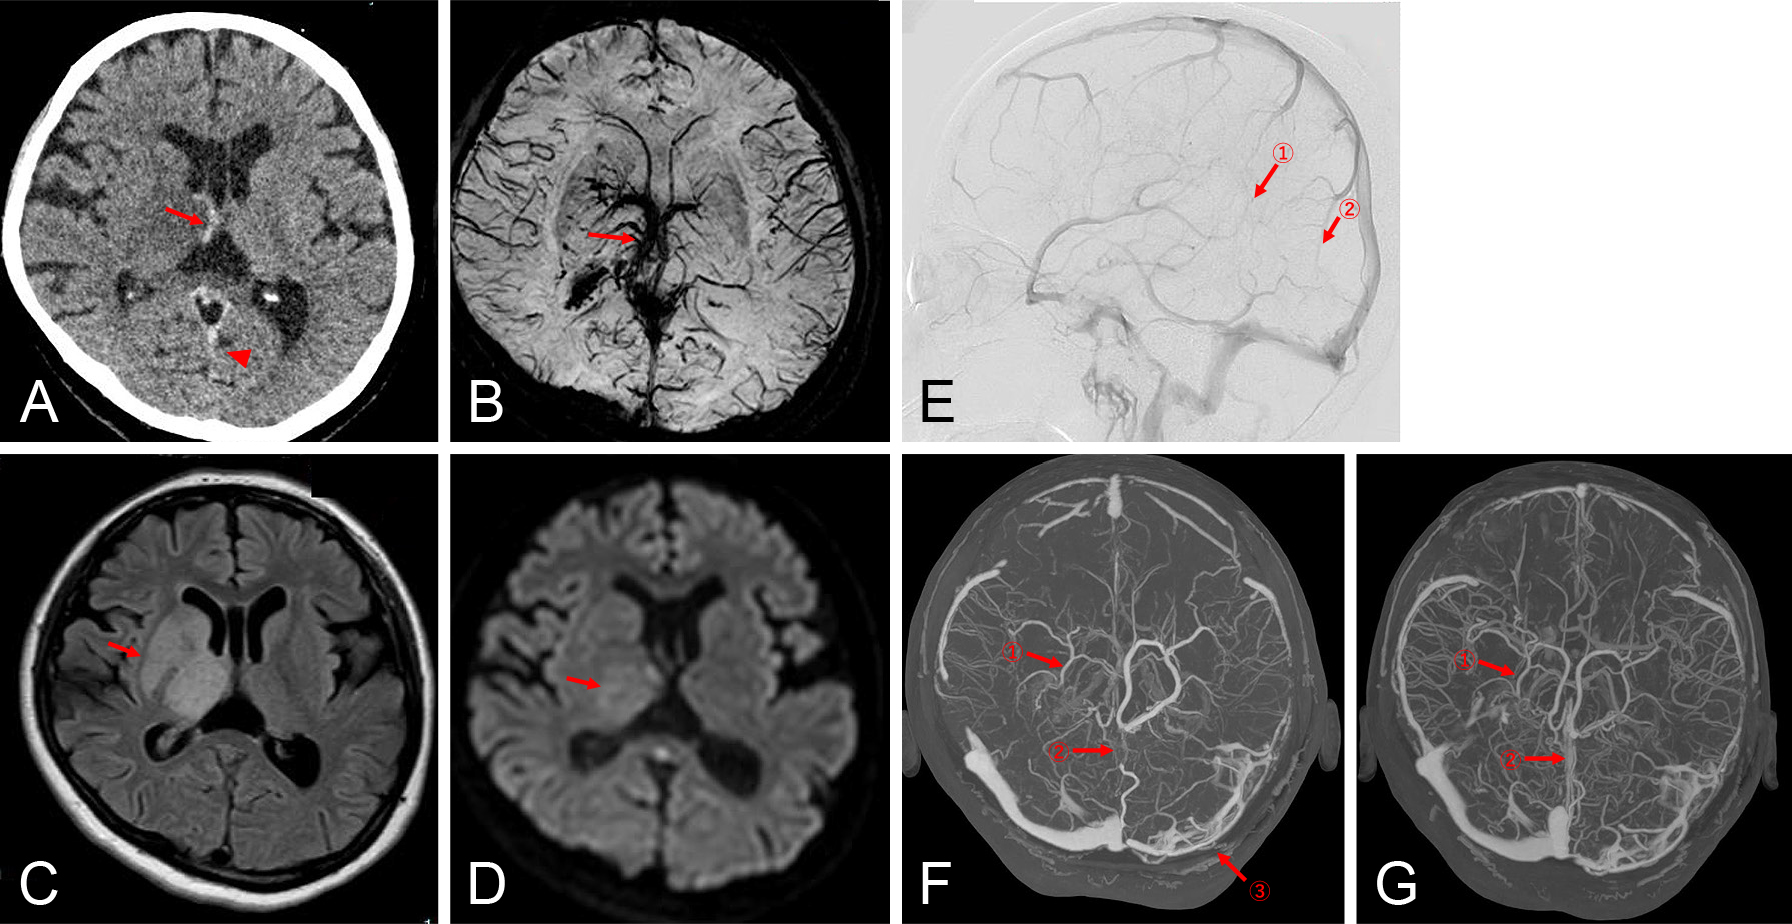

直接経口抗凝固薬内服にもかかわらず脳梗塞を発症した心房細動患者に対する経皮的左心耳閉鎖術:症例報告

Percutaneous left atrial appendage closure for atrial fibrillation-related ischemic stroke despite direct oral anticoagulation: a case report

川端 健新, 江頭 柊平, 村松 恭祐, 逸見 文昭, 宇羽野 恵, 小西 明範, 大森 奈美, 山口 徹雄, 児玉 隆秀, 上坂 義和

Kenshin Kawabata, Shuhei Egashira, Kyosuke Muramatsu, Fumiaki Henmi, Megumi Ubano, Akinori Konishi, Nami Omori, Tetsuo Yamaguchi, Takahide Kodama, Yoshikazu Uesaka

2026/02/13